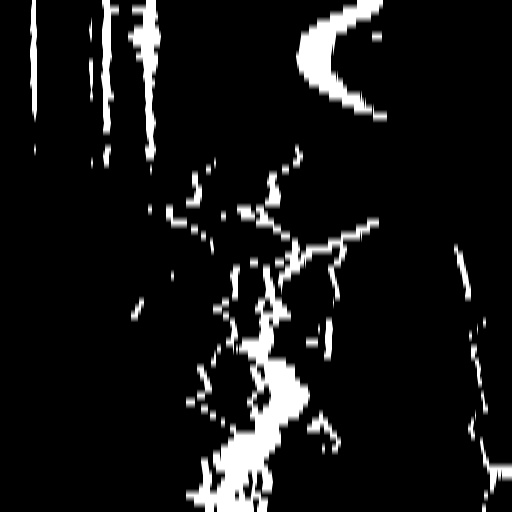

Segmenting vascular regions from X-ray images through unsupervised methods is a highly challenging task. To facilitate our subsequent work, we employ a Hessian-based filter [16] to generate a set of binary masks that crudely represent blood vessel regions. Specifically, our approach comprises the following two steps:

(1) Apply a Hessian-based filter to the entire sequence. The output pixel intensities range from 0 to 255, with higher numerical values indicating a stronger presence of tubular structural features.

(2) Based on the outputs from step (1), calculate the overall intensities of the entire image and set an appropriate threshold to convert them into binary images. We use Otsu’s method [49] to automatically determine the threshold. The purpose of selecting the threshold is to ensure that images with higher intensities correspond to larger vascular areas. Finally, we employ a region-growing post-processing technique to eliminate noise.

Additionally, we use a pre-trained optical flow model, RAFT [63], to generate the initial optical flow between consecutive frames. We illustrate the preprocessing steps in Fig. 2 (a).